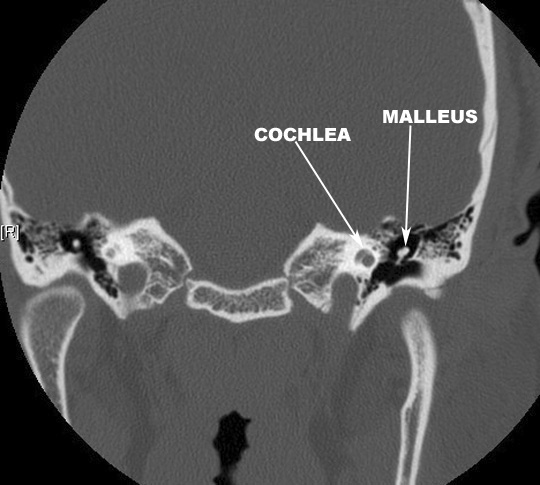

Identify the malleus and cochlea. Click the image for labeling.